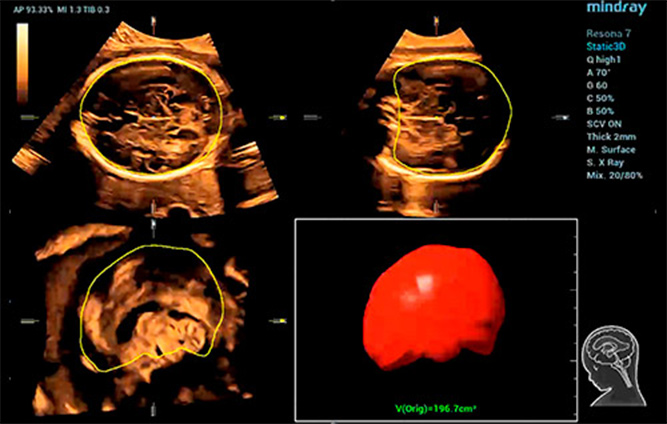

Afin de rĂŠduire la dĂŠpendance Ă l'utilisateur et d'amĂŠliorer l'efficacitĂŠ du diagnostic, Mindray a dĂŠveloppĂŠ une interaction?3D/4D innovante basĂŠe sur des scĂŠnarios cliniques d'examen ĂŠchographique?3D tels que le cerveau, le visage, la colonne vertĂŠbrale et les os longs du f?tus, ce qui permet d'automatiser l'identification de la vue, l'optimisation de l'imagerie, l'acquisition des plans et la quantification en un seul clic. Le flux de travail est vĂŠritablement automatique tout au long de la procĂŠdure, et apporte une grande confiance envers le diagnostic pour de meilleurs soins au patient.

Smart Planes CNS

Smart ICV?: calcul automatique du volume intra-cr?nien